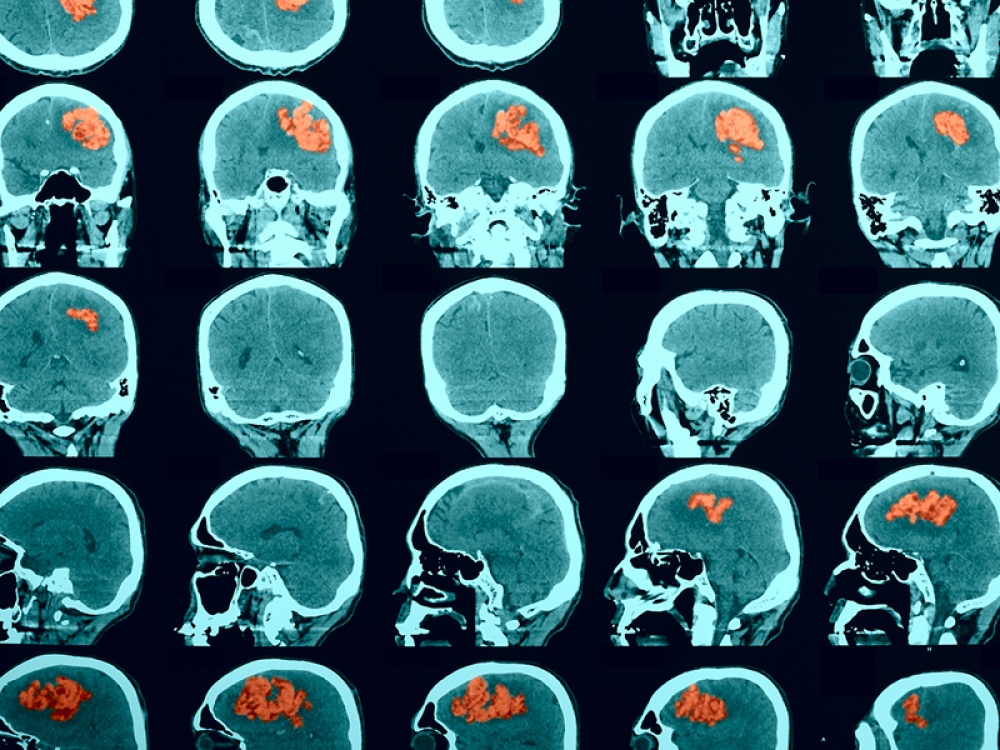

Encephalitis is an inflammation of the brain caused by an infection (such as measles, flu and, recently, Covid-19) or through the immune system attacking the brain in error. Unfortunately, it has a high death rate and many of the survivors of the condition are left with an acquired brain injury. Staggeringly, 500,000 people are affected by encephalitis globally each year.